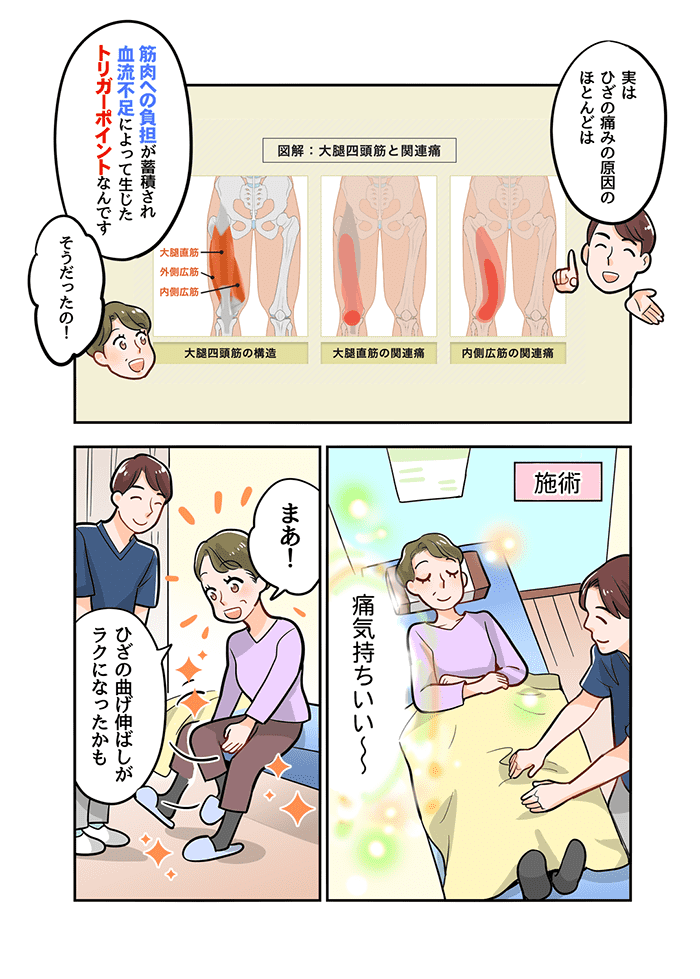

膝の痛みを解消するためには膝の変形を治すことではなく、膝の変形によって膝の筋肉にかかって発生したトリガーポイントを改善することが痛みを取り除くには最善の方法なのです。

下記図は膝を安定させるために大いに働く大腿四頭筋という筋肉にトリガーポイントが発生した際に痛みの出る範囲です。図からもわかるように膝の内側などを中心に痛みを感じます。※専門用語で関連痛と言います。